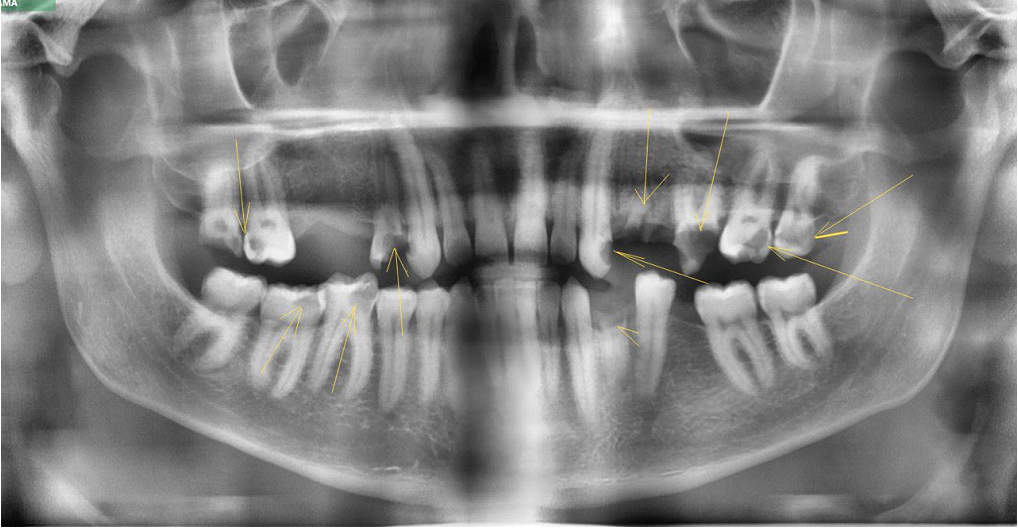

Это фронтальная панорама. Серьги тут видно в овалах по бокам, а в прямоугольниках видно, как отражения от них перекрывают корни зубов.